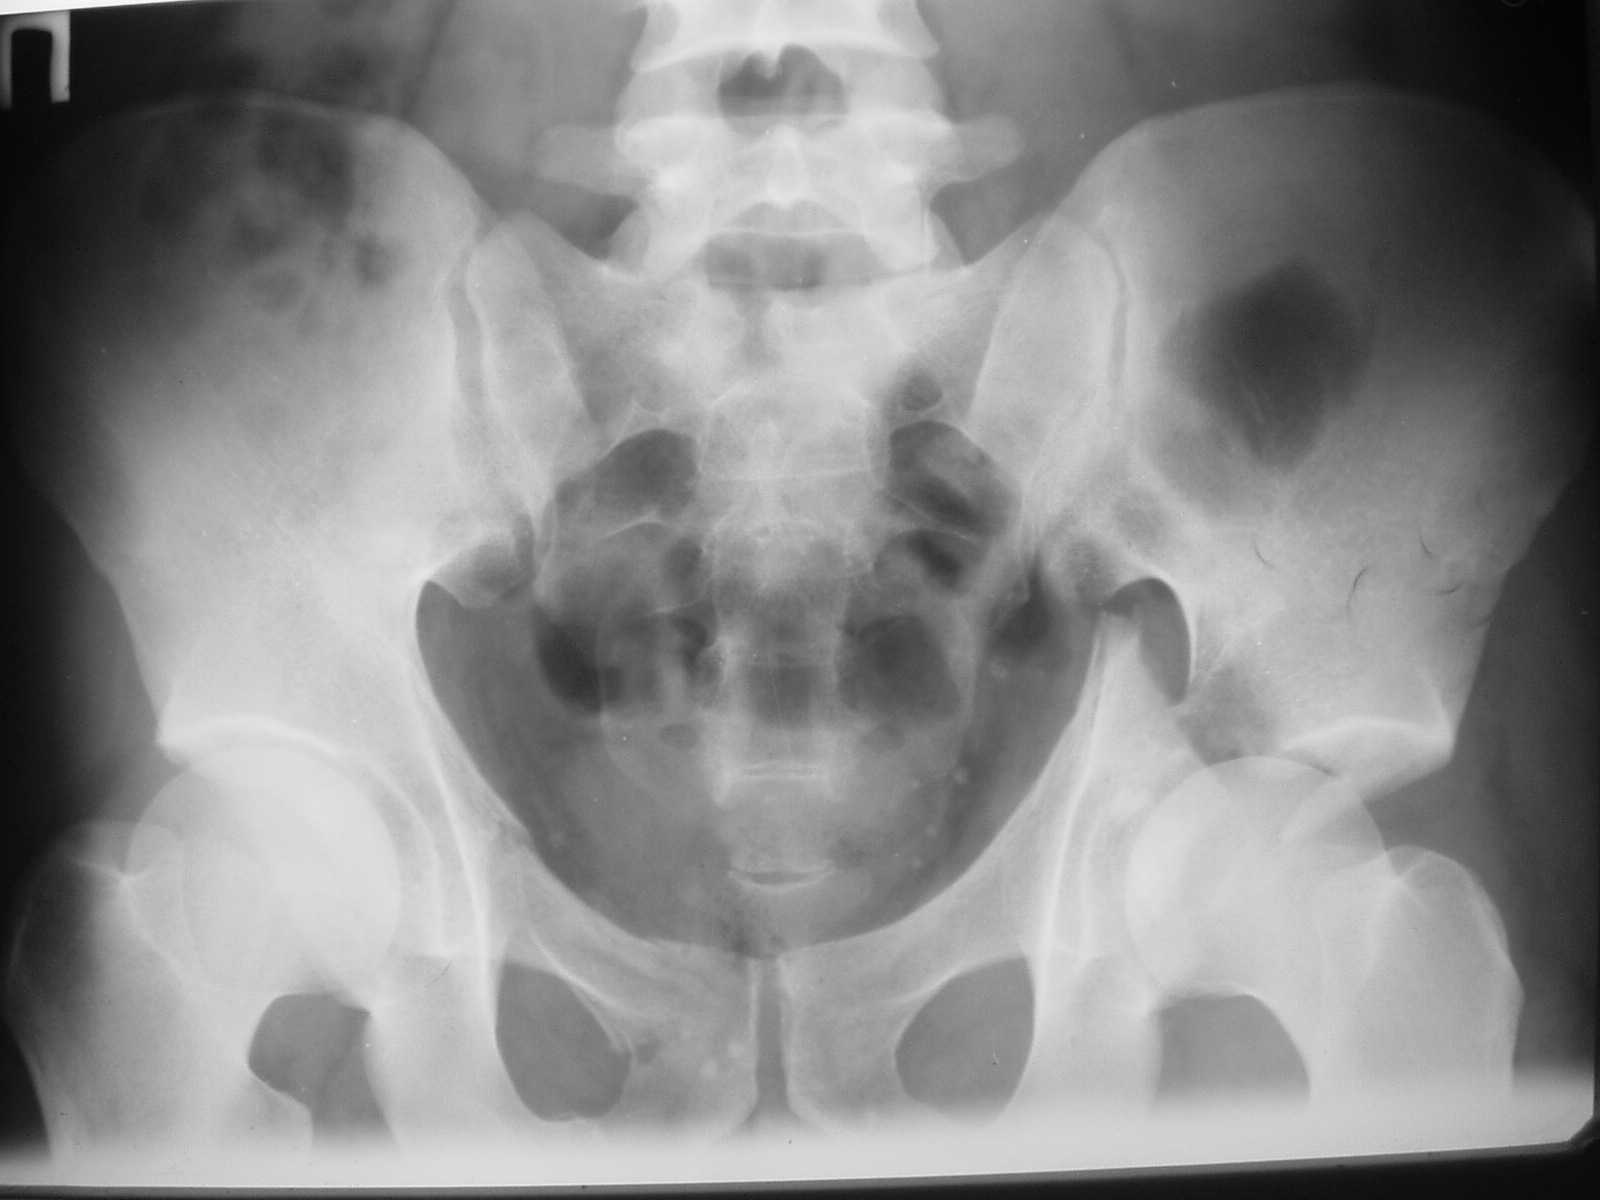

The details of the fracture are not so clear from the images sent...would you be able to send along an AP and Judet images as well as some additional axial images above and below the joint?

Without complete CT images and/or oblique radiographs, it's difficult to answer your question definitively, but it appears that there may not be a posterior wall fracture that requires a posterior approach. A successful reduction through an ilio-inguinal approach will have a faster recovery, and not risk SGN injury or heterotopic ossification.

Here are some more axial images. What is your opinion as for the timing of the operative treatment?